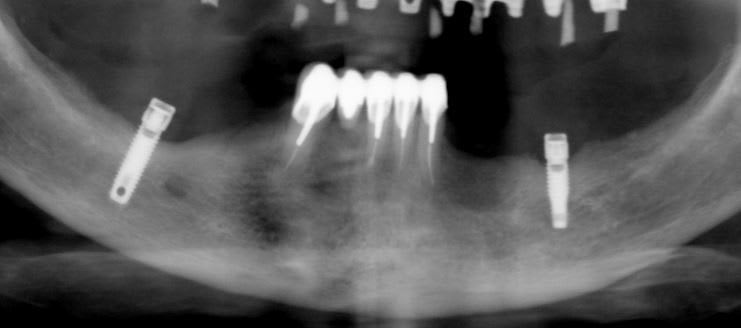

auriez-vous un idée de la marque de cet implant posé il y a plus de vingt ans.

Steri-oss

Composants prothétiques pour ainsi dire introuvables maintenant…..désolé mais songe plutôt à déposer…..

Nobel distribue toujours des gaines calcinables rotationnelles, des transferts et des analogues.